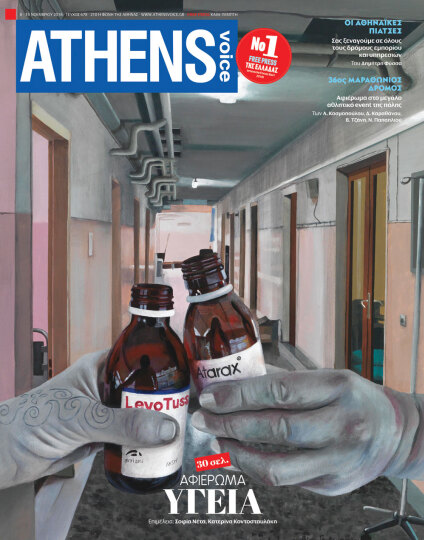

Αυτή την εβδομάδα το σχεδιάζει η Βίκυ Γεωργιοπούλου. Ζει και εργάζεται στην Αθήνα. Γεννήθηκε το 1975 στην Καλαμάτα. Μαθήτευσε στο εικαστικό εργαστήρι του Δήμου Καλαμάτας και το 1999 αποφοίτησε με άριστα από την Ανωτάτη Σχολή Καλών Τεχνών Αθήνας με δάσκαλο τον Χρόνη Μπότσογλου. Έχει λάβει μέρος σε πολλές ομαδικές εκθέσεις στην Ελλάδα και το εξωτερικό. Το 2004 φιλοτέχνησε το εξώφυλλο του βιβλίου «Best of Athens», της ATHENS VOICE, και το 2009 έργο της έγινε εξώφυλλο στην ίδια εφημερίδα. Έργα της υπάρχουν σε ιδιωτικές συλλογές. Αυτές τις ημέρες παρουσιάζει στην αίθουσα Περί Τεχνών Καρτέρης (Ηροδότου 5, Κολωνάκι) την 6η ατομική της έκθεση με τίτλο «εις υγείαν», μέχρι 8/12/18.